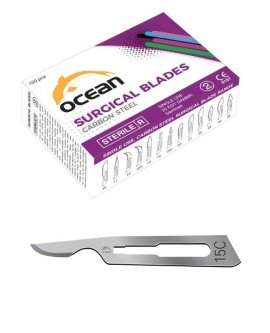

Ürünlerimiz